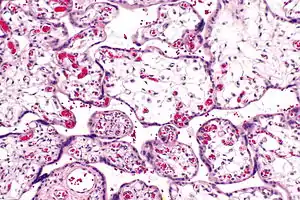

Placental villous immaturity

Placental villous immaturity is chorionic villous development that is inappropriate for the gestational age.

| Micrograph of villous immaturity. H&E stain. | |

Immature chorionic villi are larger and have more central blood vessels; thus, the diffusion distance for gas and nutrient exchange is larger and, therefore, placental function is impaired.